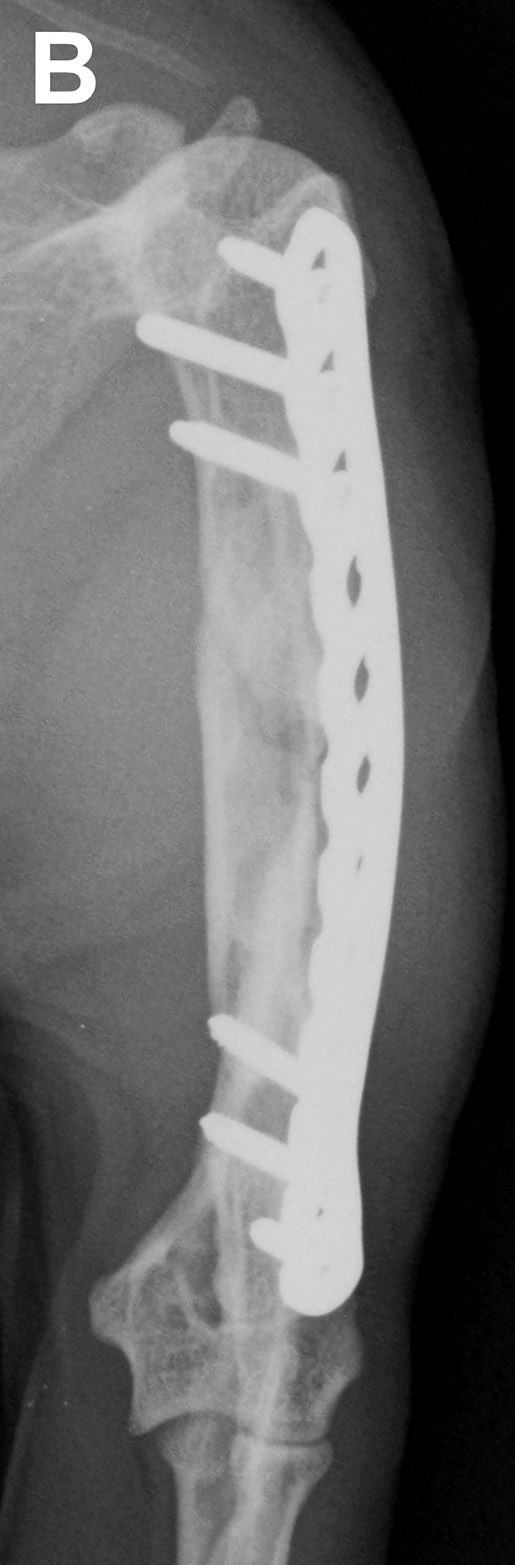

Fig 6 – Post-operative maximal intensity projection CT images.

Fig 8 – Four month follow-up radiographs showing almost complete bridging of the fracture site with mineralised callus.